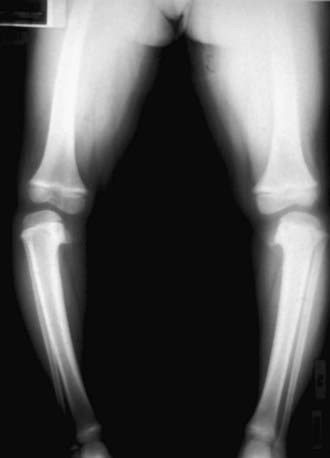

An anteroposterior standing radiograph of both lower extremities with patellas facing forward and a lateral radiograph of the involved extremity should be obtained (Fig. 667-10). Weight-bearing radiographs are preferred and allow maximal presentation of the clinical deformity. The metaphyseal-diaphyseal angle can be measured and is useful in distinguishing between physiologic genu varum and early tibia vara (Fig. 667-11). Langenskiöld has six stages on radiographs (Fig. 667-12). The differentiation is based on fragmentation of the epiphysis, beaking of the medial tibial epiphysis, depression of the medial tibial plateau, and formation of a bony bar. Occasionally, CT with three-dimensional reconstructions, or MRI, may be necessary to assess the meniscus, the articular surface of the proximal tibia including the posteromedial slope, or the integrity of the proximal tibial physis.

image

Figure 667-10 Anteroposterior radiograph of both knees in Blount disease.